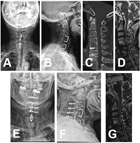

对于病变为单节段ASD且不伴有后纵韧带骨化的8例患者采用Zero-P钢板植入ACDF术。麻醉满意后,患者取仰卧位,颈部呈过伸状态。手术入路选择避开前次手术切口,于原切口的对侧行横形切口。沿胸锁乳突肌内缘做钝性分离,经颈内脏鞘与血管鞘间隙进入椎体前缘,小心分离颈前钢板与食道间隙,根据手术节段的需要显露出钢板的远端或近端。C臂X线机透视再次确定责任椎间隙。于责任椎间隙的上下椎体置入Caspar撑开器定位螺钉,保留前次手术置入的钢板,撑开器螺钉选择合适的位置置入。安置好Caspar撑开器后适当撑开椎间隙,彻底切除责任节段椎间盘髓核组织,直至硬膜囊显露清楚,减压彻底后取合适型号的Zero-P钢板置入椎间隙,并用2枚螺钉固定牢靠(图1)。